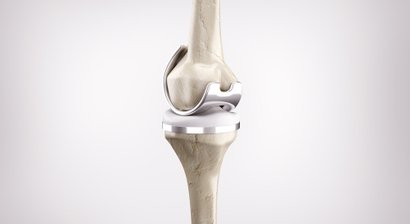

Halbschlittenprothese (Teilgelenkersatz Knie)

3D gestützter Kniegelenkersatz (MyKnee®) / Knieendoprothetik

Mein fachärztlicher Schwerpunkt liegt in der Behandlung des Kniegelenks. Durch die internationale Ausbildung an einer Knieklinik, aktive Mitgliedschaft in zahlreichen wissenschaftlichen Fachgesellschaften sowie langjährige Erfahrung führe ich auch komplexe Knieoperationen (u.a. Meniskustransplantation) und Kombinationseingriffe in höchster Fallzahl in Wien durch.